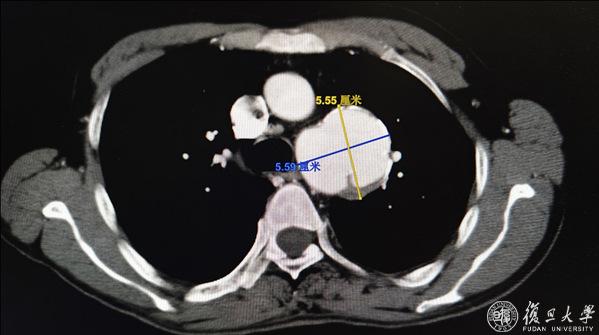

抵达上海的当日中午,格桑旦增病症骤然加重,由痰中带血迅速发展为咯血,心急如焚的姐姐联系了血管外科董智慧教授和方刚医生。董教授和方医生初步判断可能为胸主动脉假性动脉瘤破裂,一旦破裂发生,很可能会导致主动脉大出血及主动脉-支气管瘘,进一步诱发失血性休克,从而导致死亡,因此建议患者立刻至血管外科急诊就诊。血管外科总值班方圆医生立即为格桑旦增进行主动脉CTA检查,发现一颗巨大的假性动脉瘤盘踞在胸主动脉,万幸的是,瘤体尚显完整,暂无破裂征象,然而,这颗巨大的假性动脉瘤就像一颗不定时血管“炸弹”,在其爆炸之前拆除它是当前的第一要务。情况紧急,为便于生命体征监测及可能发生的急重症抢救,急诊立即将格桑旦增收治入监护室,暂时稳住了病情。

巨大的胸主动脉假性动脉瘤